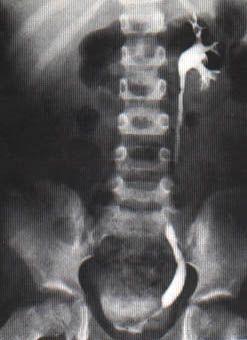

正常肾盏和肾盂内尿量仅5~10ml。尿路持久梗阻后,梗阻上部扩大,肾盏肾盂显著增大,肾髓质破坏,皮质呈硬化薄层。

相关图片